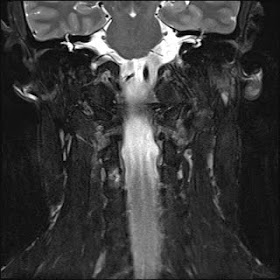

Facetal Osteoid osteoma

Note: tiny hypointense nidus.